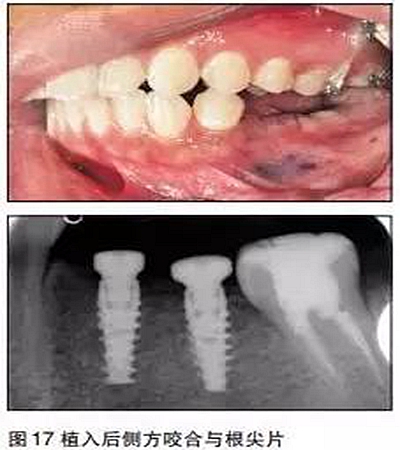

③用骨鑿去除部分牙槽嵴頂骨質(zhì),球鉆定位,逐級(jí)備洞,植入2枚NobelActivie4.3×10mm種植體,植體植入初期穩(wěn)定性35N;

④上愈合基臺(tái),一期縫合。

三個(gè)月后

采用閉口印模法取模,比色,送技工中心制作。

口內(nèi)就位

最后修復(fù)體在口內(nèi)就位,35N鎖緊螺絲,封閉螺絲口,納米樹脂充填螺絲開口,調(diào)牙合,拋光完成。